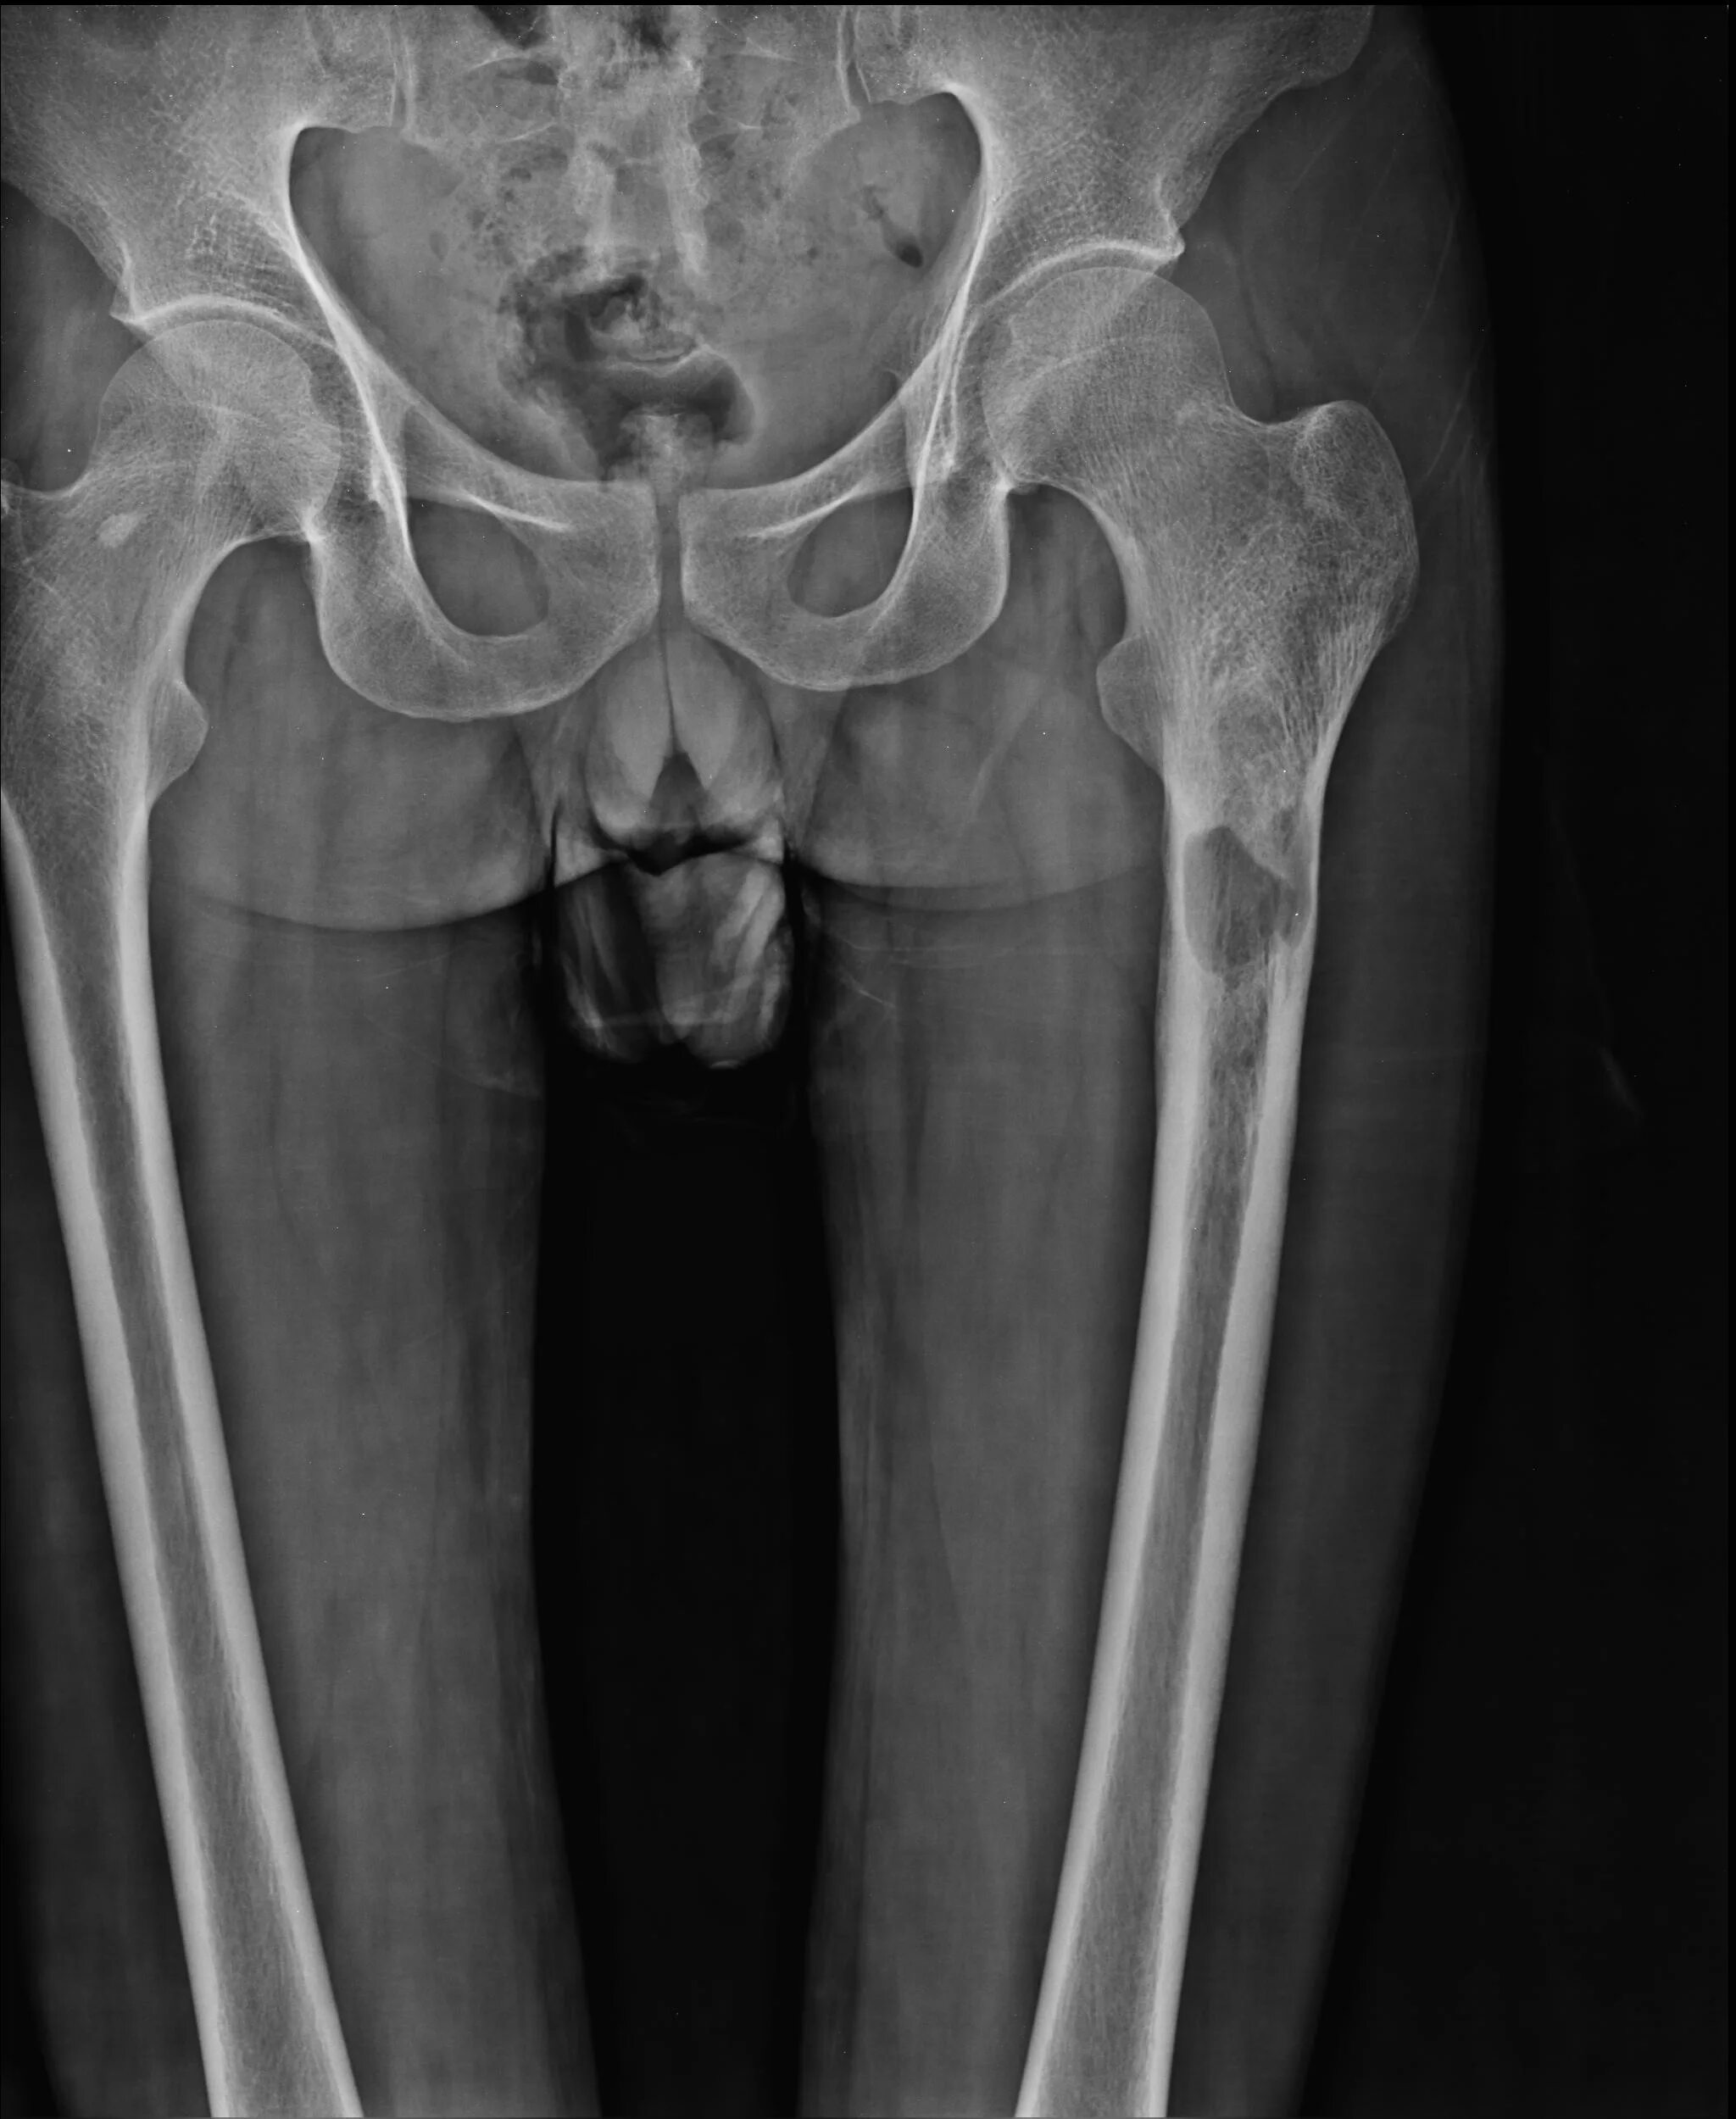

Метастазы в тазобедренном суставе